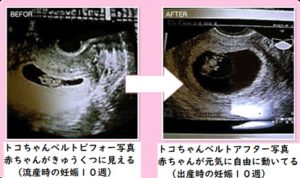

トコちゃんベルトの着用により、骨盤のゆるみが6cm改善した子宮の写真

左は前回流産時の子宮内の胎嚢画像。 施術しながら体外受精で妊娠し、右は、出産時の10週時の子宮内の胎嚢画像。

子宮内の胎嚢の形状が尖っているのと、骨盤のゆるみは5センチ以上ありました。 子宮内の胎嚢の形状が尖っていると流産しやすいという見解を持つ産婦人科医もいます。 ※必ずしも子宮内の胎嚢の形状が丸く改善しないと流産するわけではありません。

そこで、トコちゃんベルト正しい着用を勧めました。 1週間後来院すると、骨盤のゆるみが2センチに改善していました。 無事出産報告がありました。

左はトコちゃんベルト着用前(7㎝の骨盤のゆるみ)⇒右は着用後(2㎝の骨盤のゆるみ) 流産歴が数度あり、今回の妊娠後も出血など不安定で来院。

左の写真で骨盤のゆるみが7㎝以上あり、子宮内の胎嚢の形状が悪いので、トコちゃんベルトを正しく着用を指導しました。 着用後は右の写真、丸くふっくらとした子宮内の胎嚢の写真になりました。(2㎝の骨盤のゆるみ) その後無事に出産されました。喜びの手紙を頂きました。